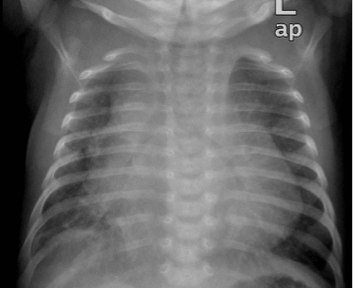

CXR

APLS Case#17 Myocarditis

By Ali Hasan